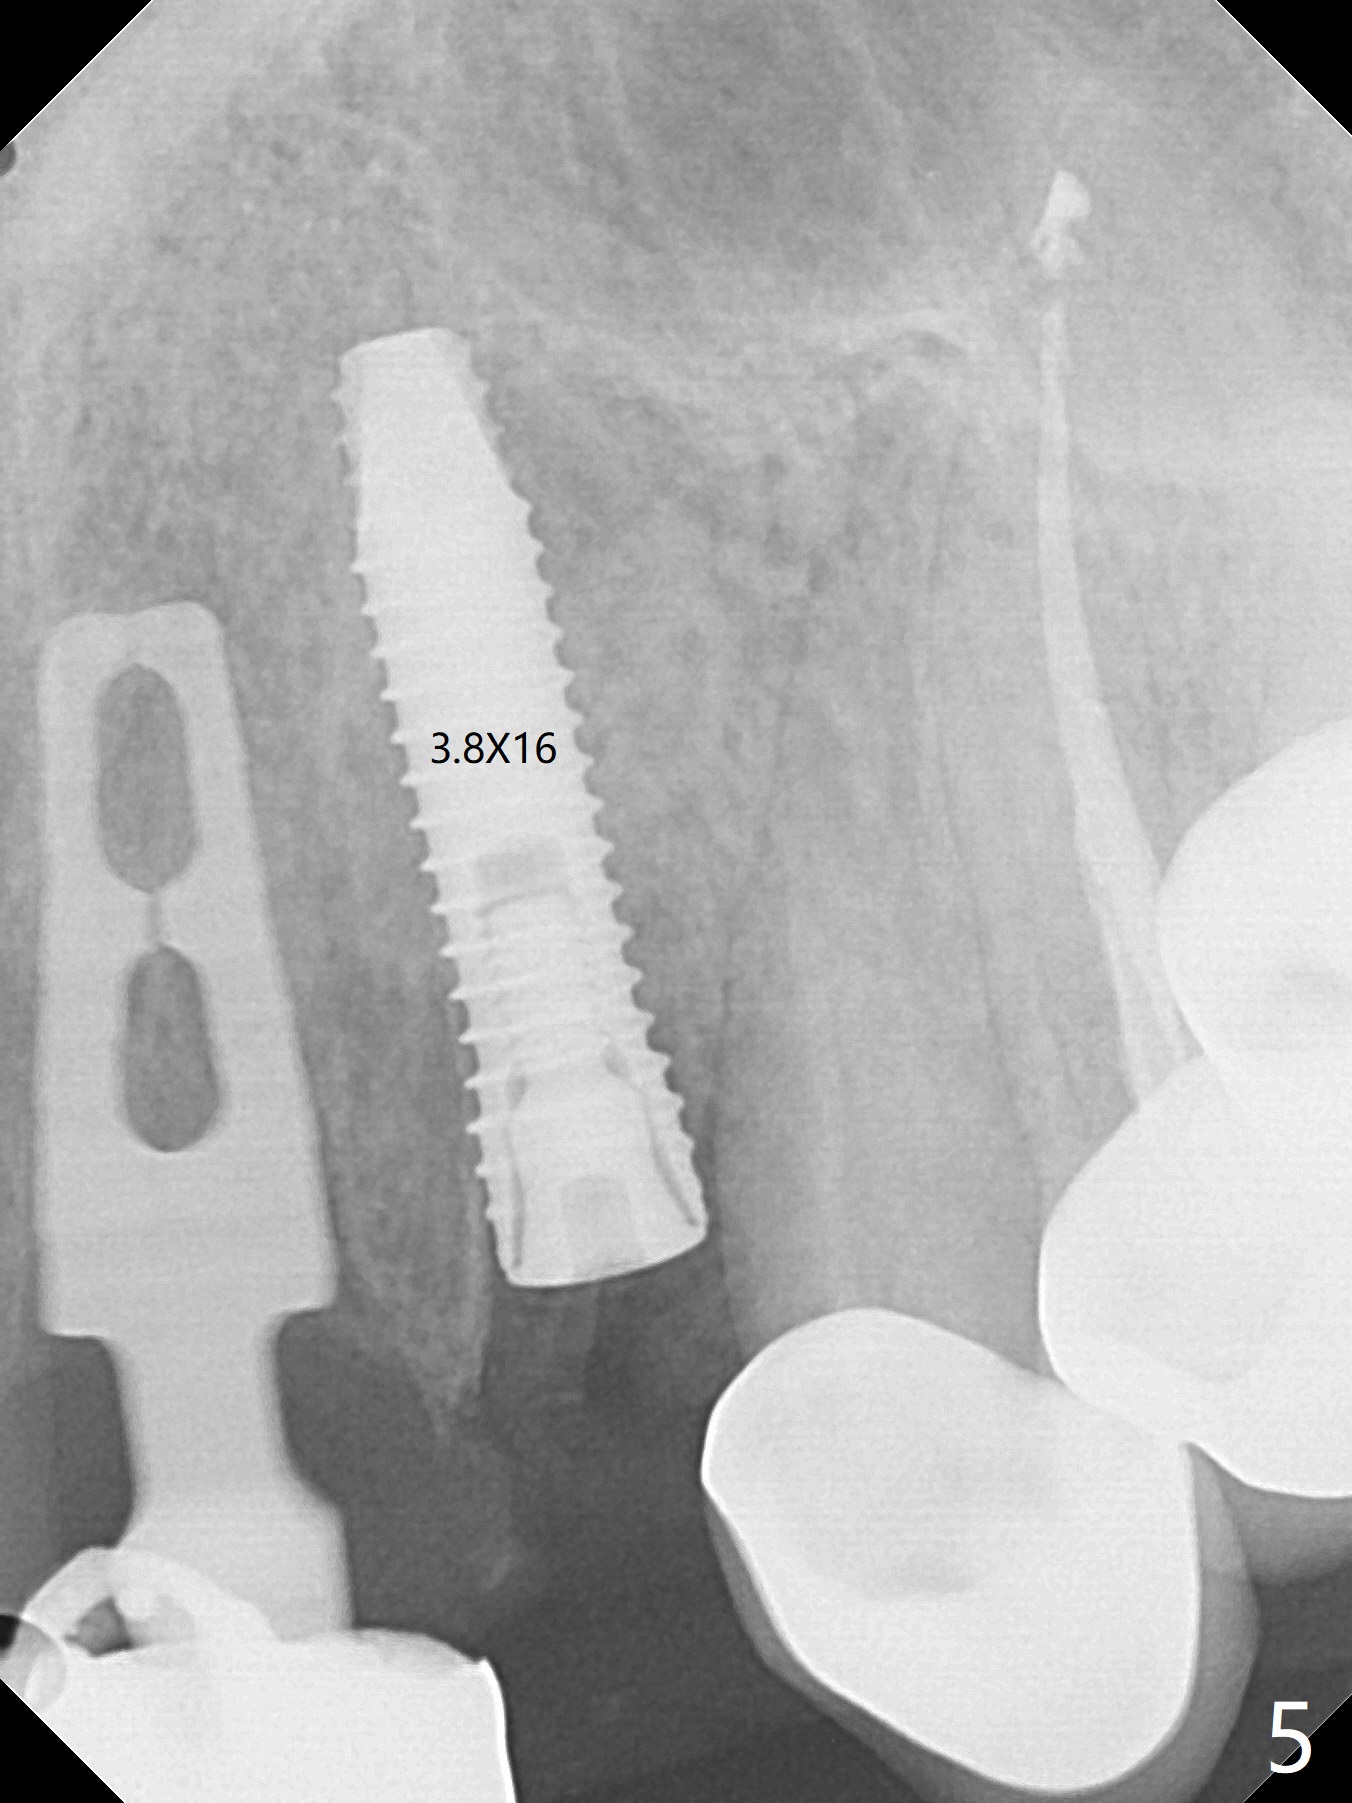

上前牙桥撤除显示右上1,2牙齿以及左上2叶片状植体好像可以保留,而左上3牙齿不能(图一,二(<:托牙边缘压迹)),拔除左上3牙齿后, 暂时把牙桥回位(图三:FPD(已经去除左上3号牙牙冠))作为3号牙种植位置参考(图四至六(G:骨粉))。其实植入前,当最后一个钻头还在原位,将PRF膜和粘性骨放置颊侧根尖(但愿骨粉能放深点),因为那里骨质很薄,好像缺损。由于植体扭力很低(大约5Ncm),放置骨粉覆盖植体(图七),为了不用缝线,涂牙周胶水(图八),放置胶原膜(图九),再涂胶水(图十)固定,最后利用右上1,2号牙(去龋,build-up后)和左上2植体制作临时牙桥,并且覆盖左上3牙槽窝。术后即刻CT显示植体颊侧(B)骨粉(图十一:*)。<:植体根尖仍有间隙,植体应该再长2毫米,初步稳定性会好些。左上3植牙愈合后,将与左上2植体制作左上1-3悬臂桥,右上1,2号牙将做根管治疗,桩,牙冠。临时牙桥术后十一天松动,右上一,二牙牙髓活性测定正常,深洗后,再次build up,不小心把左上3胶原膜吹掉,下面骨粉还稳定。术后三周病人回来做右上六种植,前牙临时修复体(图十二)需要修改(图十三)。拍摄三个方向照片显示前牙牙龈乳头(颊侧和咬合面)。